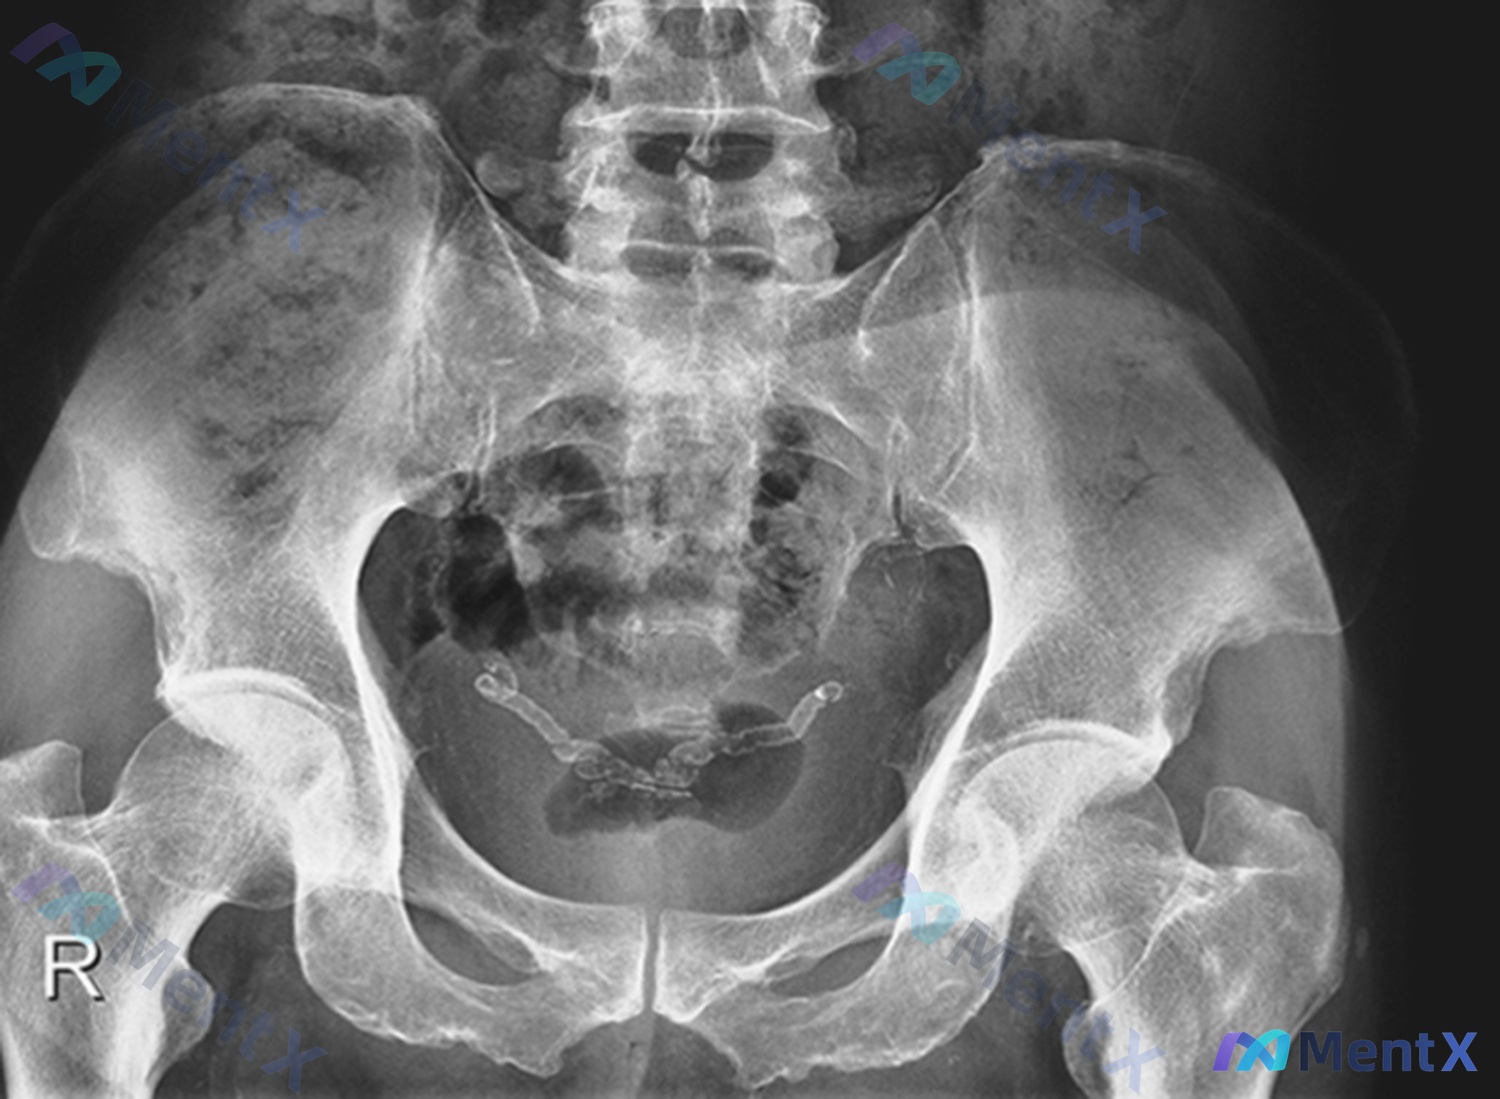

这是一张骨盆正位X光片:

- 投照质量:基本对称,无明显旋转,对比度和视野都符合要求;

- 骨骼与关节:骨盆环连续,未见骨折/脱位;双侧髋关节、骶髂关节、耻骨联合间隙清晰,沈通氏线连续,关节面无模糊/硬化/侵蚀;骨密度、骨小梁也都正常,没有溶骨或成骨性改变;

- 软组织与异物:盆腔中部(膀胱区附近)见一枚“Y型/多节段相连”的高密度金属影,形态符合宫内节育器(IUD),位置居中,无明显移位;其他软组织无肿胀、积气或钙化。